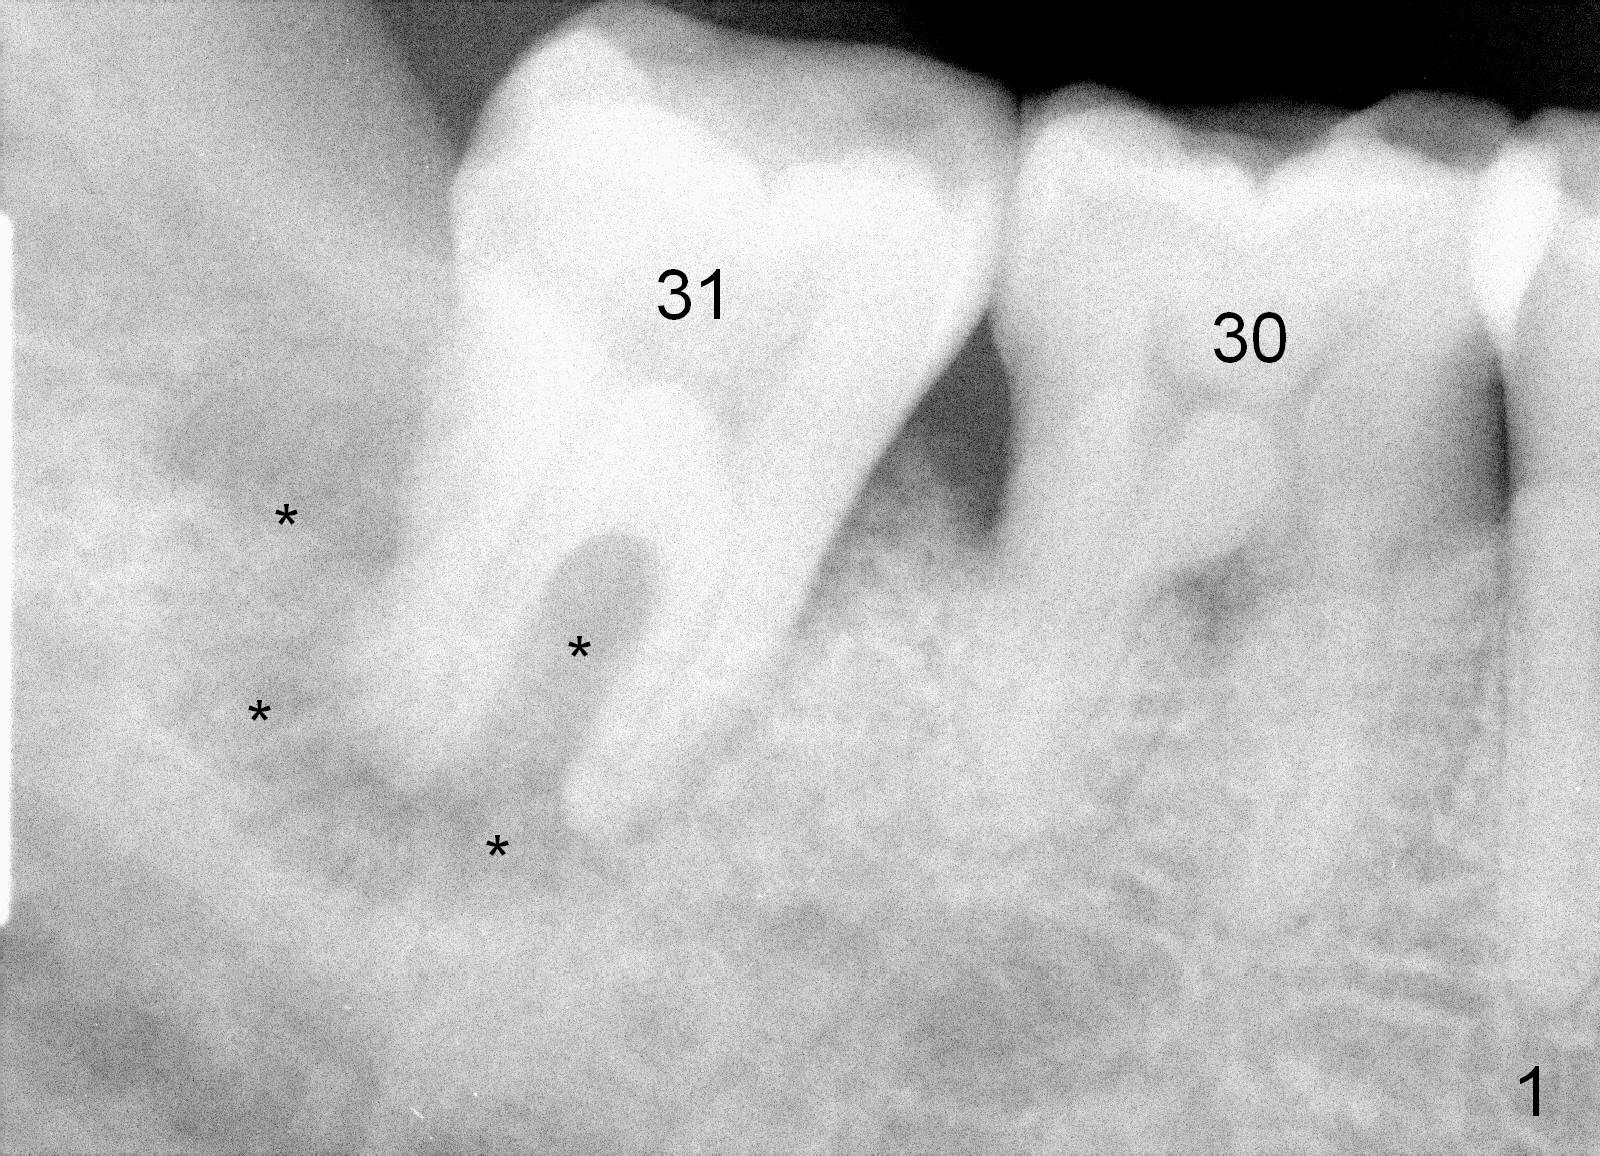

One year and a half years ago, the tooth #31 of a 48-year-old man had infection (Fig.1 *) and was extracted without implant. There was more bone loss in the distal of #30 than in the mesial (Fig.2 *). Recently the patient returns with infection at #30 distally with severe bone loss (Fig.3 *). An immediate implant is to be placed mainly in the mesial socket (Fig.4 (bone-level), Fig.5 (tissue-level)).